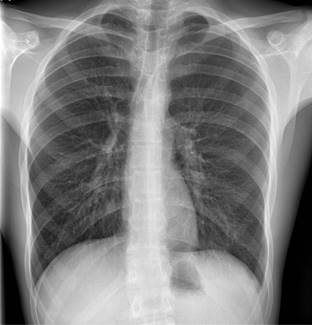

Seis horas después, refiere dolor intenso a pesar de analgesia, por lo que se toma nueva radiografía, observando aumento del neumotórax al 20% (Figura 2). Se decide colocación de drenaje torácico en segundo espacio intercostal izquierdo con posterior aspiración con Pleur-evac®. El control radiológico a las 12 horas se observa con mejoría, por lo que se cierra aspiración. Sin embargo, a las 18 horas el paciente presenta empeoramiento del dolor torácico de características pleuríticas, a lo que se agregó drenaje de líquido hemático de aproximadamente 300 mL, sospechando de hemotórax. El hematocrito fue de 48%.

Figura 2: Rx tórax postero-anterior en bipedestación: discreto aumento del neumotórax izquierdo del 20% (moderado) según el índice de Light.